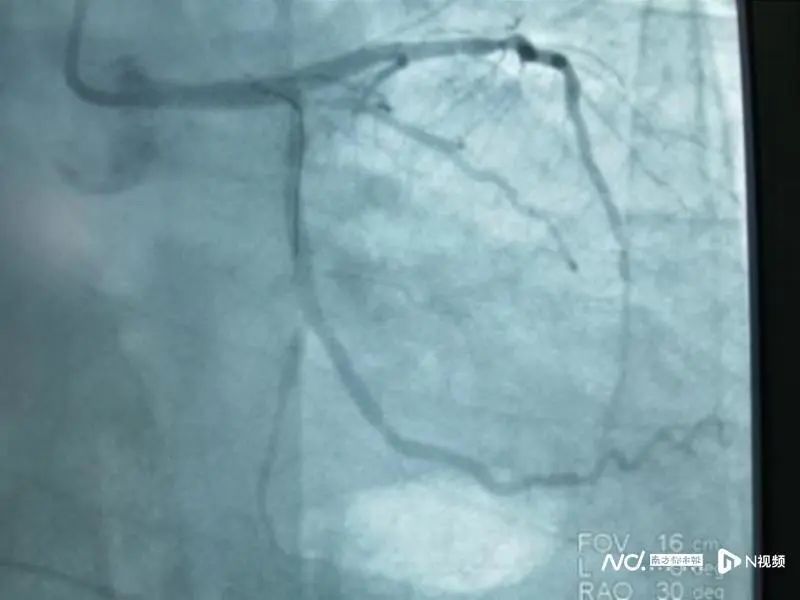

“快!快!快!”医院急诊科主任现场指挥,同时呼叫心血管内科、神经内科会诊,高度怀疑是急性心肌梗死,建议立即进行急诊冠脉介入诊疗。

抢救过程险象环生,当记者见到贺先生时,他已经从心血管内科CCU转到普通病房,正在进行康复训练。